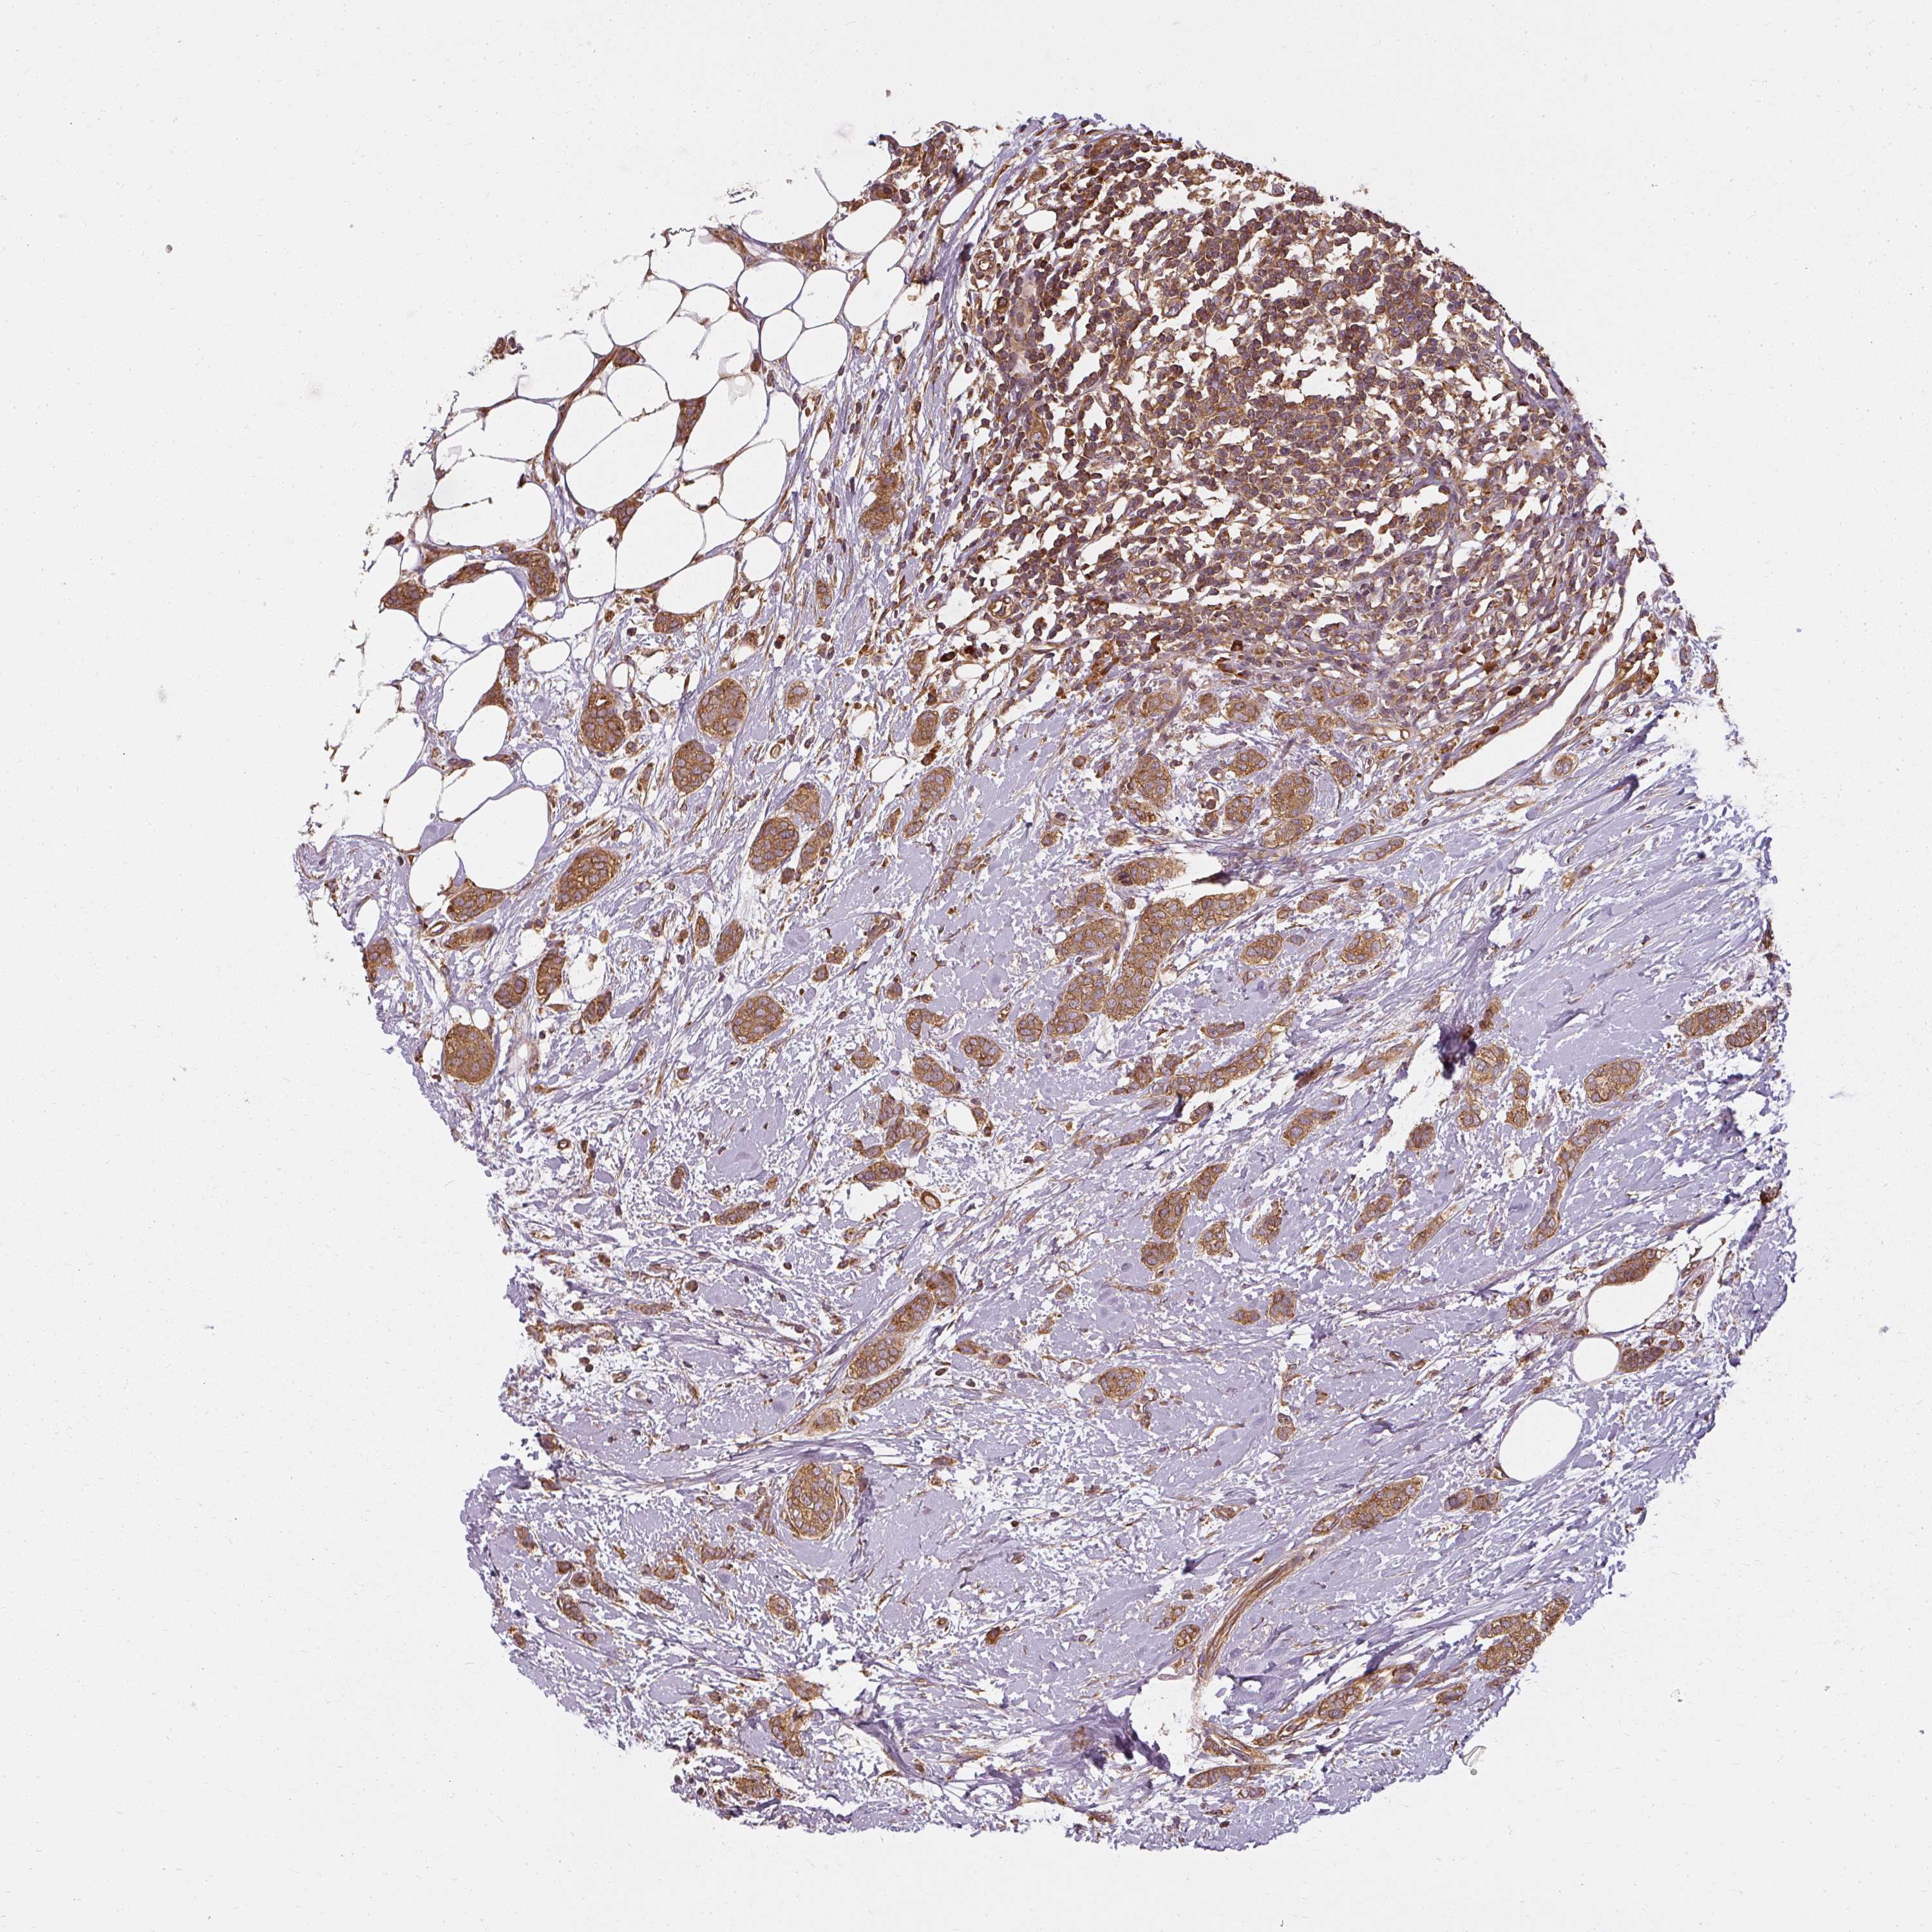

BRCA TCGA BRCA VALIDATION PROTEIN EXPRESSION

ANTIBODIES

AND

VALIDATION